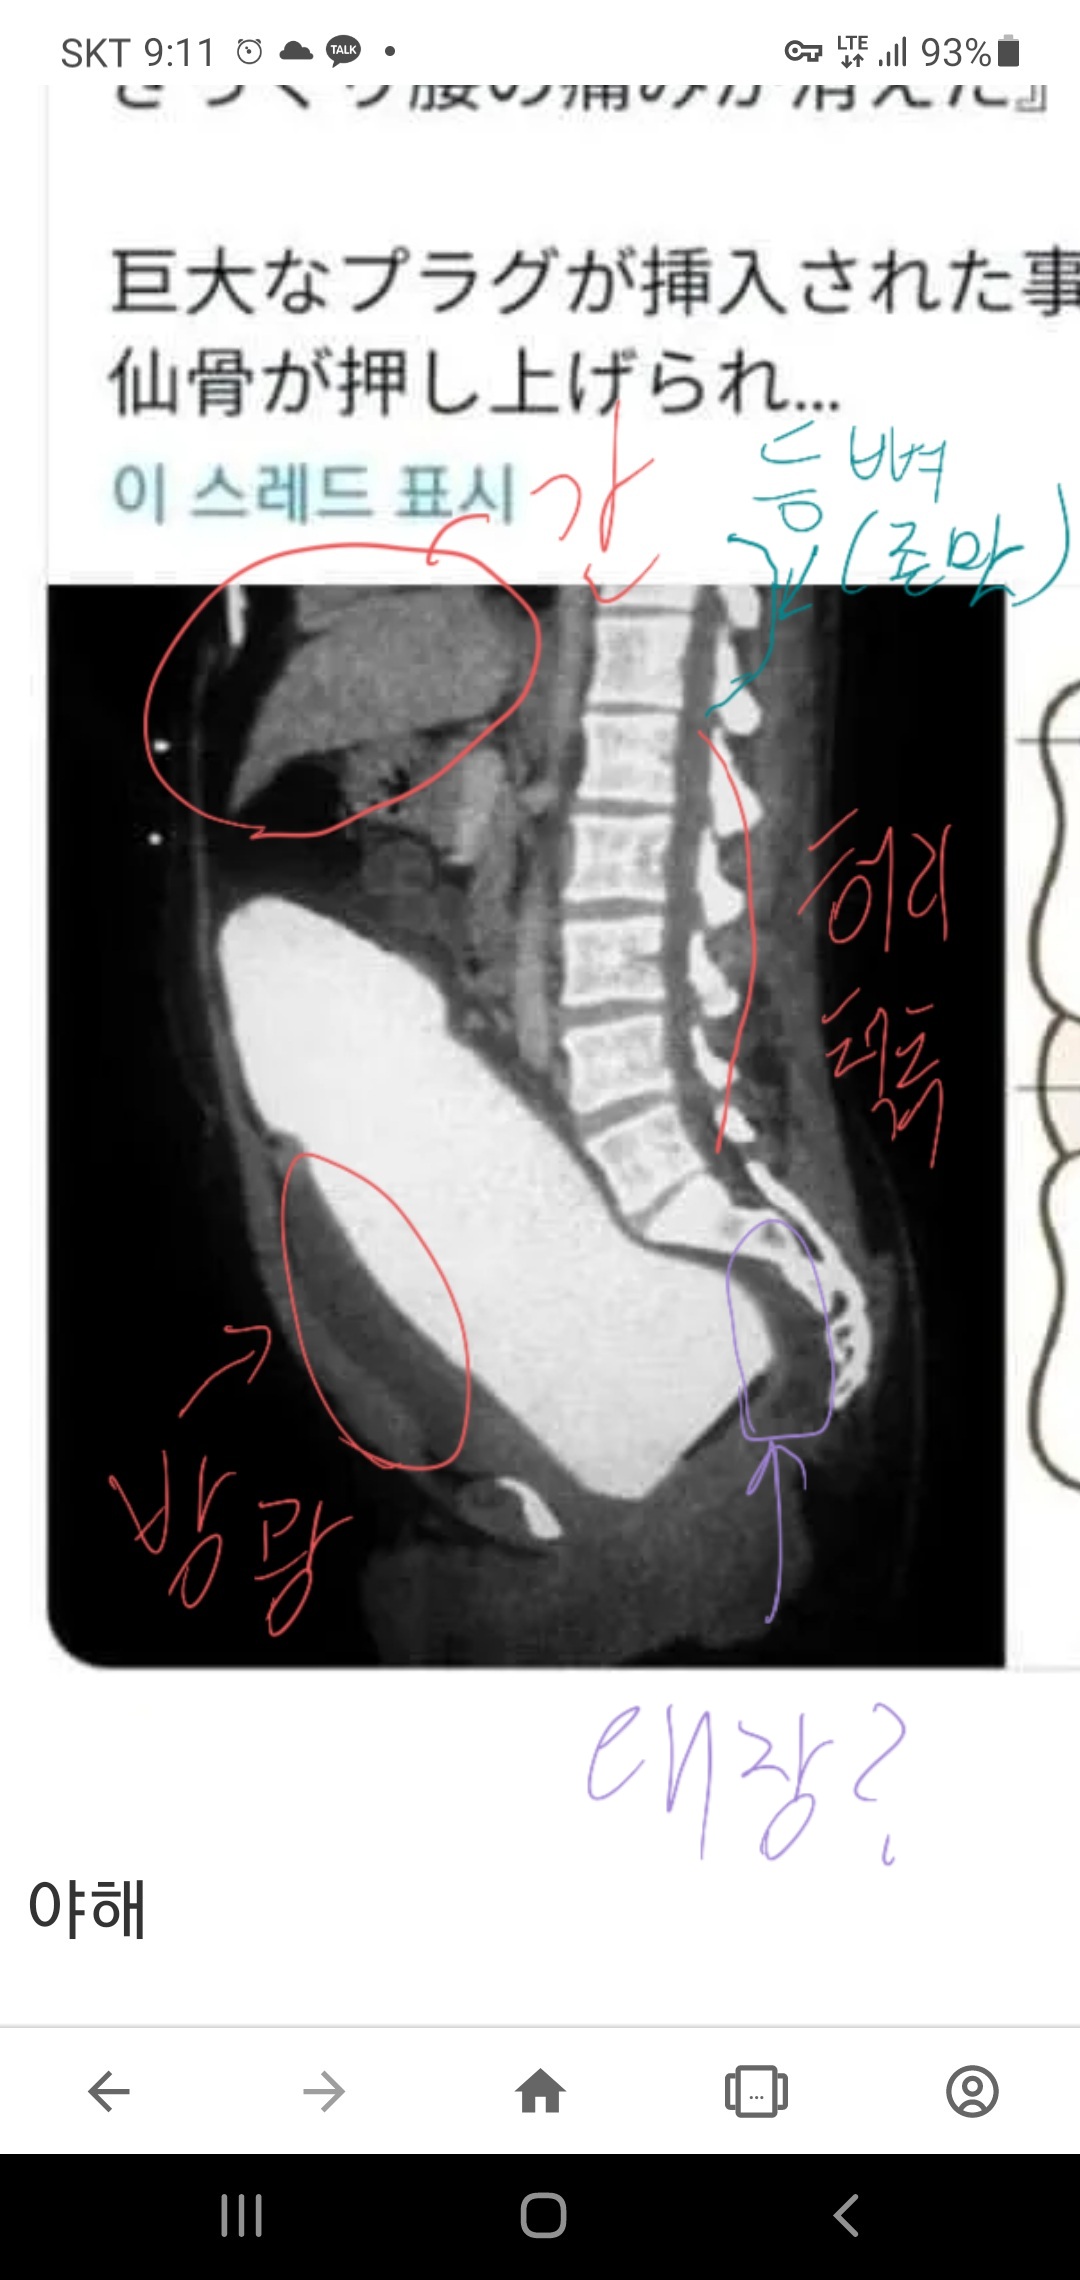

ÁúÀÌ ¹æ±¤ µÚ ´ëÀå ¾Õ¿¡ À§Ä¡Çѵ¥ º¸¸é ³Ê¹« Áþ´·Á¼ Àú°Ô »ý½Ä±âÀÎÁö ´ëÀåÀÎÁö ¾îµð¿¡ »ðÀÔÇß´ÂÁö Á¤È®È÷ ¸ð¸£°ÚÀ½. ¾Æ¸¶ »ý½Ä±â Àϰа°À½ µÚ¿¡ Ç¥½ÃµÈ ºÎºÐÀÌ ¾à°£ ¾îµÎ¿î°Ô ´ëÀå ´À³¦ ³². µôµµ ±æÀÌ´Â ´ëÃæ °è»êÇØº¸·Á Çߴµ¥ ±ÍÂú¾Æ¼ ÆÐ½º. Ç㸮ôÃß¿¡¼ ²¿¸®»À ±îÁö ³»·Á°¡´Âµ¥´Ù °£±îÁö µµ´ÞÇÒ Á¤µµÀε¥... °£Àº ¿ì¸® º¹ºÎÁß¿¡¼ »óº¹ºÎ·Î À§¿¡ À§Ä¡ÇÔ. ´ëÃæ ¹è²Åº¸´Ù À§·Î ¹ÚÇû´Ù »ý°¢ÇÏ¸é µÊ. µÎ²²´Â »çÁø¸¸ ºÁµµ »ç¶÷ ¿©¼º ¸ö ¹Ý Á¶±Ý ´ú µÇ°Ô ¹ÚÇôÀִµ¥ »ç¶÷ ¸ö Áß °¡Àå Å« Àå±âÀÎ °£ ¸¸Å Å. ½±°Ô ¸»Çϸé Àڱ⠸ö¶×¾Æ¸® ºñ½ÁÇÑ µÎ²²¿¡´Ù ¾É¾ÒÀ»¶§ ¾ûµ¢ÀÌ¿¡¼ °ÅÀÇ °¥ºñ»À ¾Æ·¡ »ì¦ ´êÀ» ±æÀÌÀÇ µôµµ¸¦ ÈÄÀåÀÌ¾Æ´Ñ ¿©¼º »ý½Ä±â·Î »ðÀÔÇØ¾ß µôµµ Ä¡·á¸¦ ´À³¥¼ö Àִٴ°Å... Âü°í·Î ¿©¼ºÀº ¸ÂÀ½.